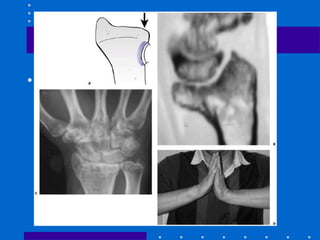

Diagnóstico - Rx

• AP + P+ Oblíquas

• AP + P com tração

• Contralateral : avaliar variância ulnar e

ângulo escafolunar

• Alguns autores indicam TC para avaliar

melhor incongruência articular

• Importante : fazer perfil com 20º de

angulação radial em direção ao feixe de RX

para avaliar fossa lunar e possível

penetração da superfície articular por

parafuso durante cirurgia

• Esta angulação retira sombra do estilóide

radial